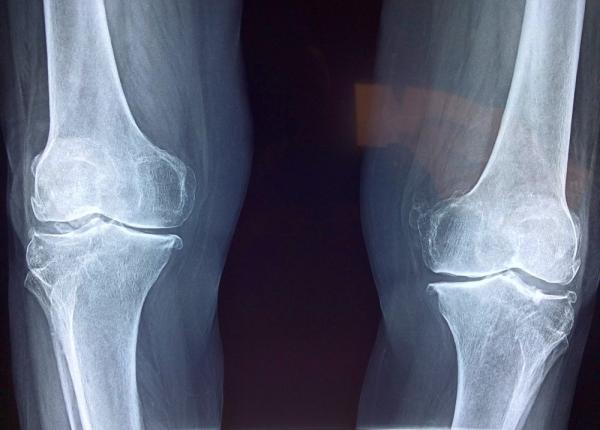

Cunoscutul medic-scriitor Vasi Rădulescu mai demontează un mit, cel al remediilor naturiste sau rapide pentru monturi. Un singur lucru funcționează cu adevărat, spune...